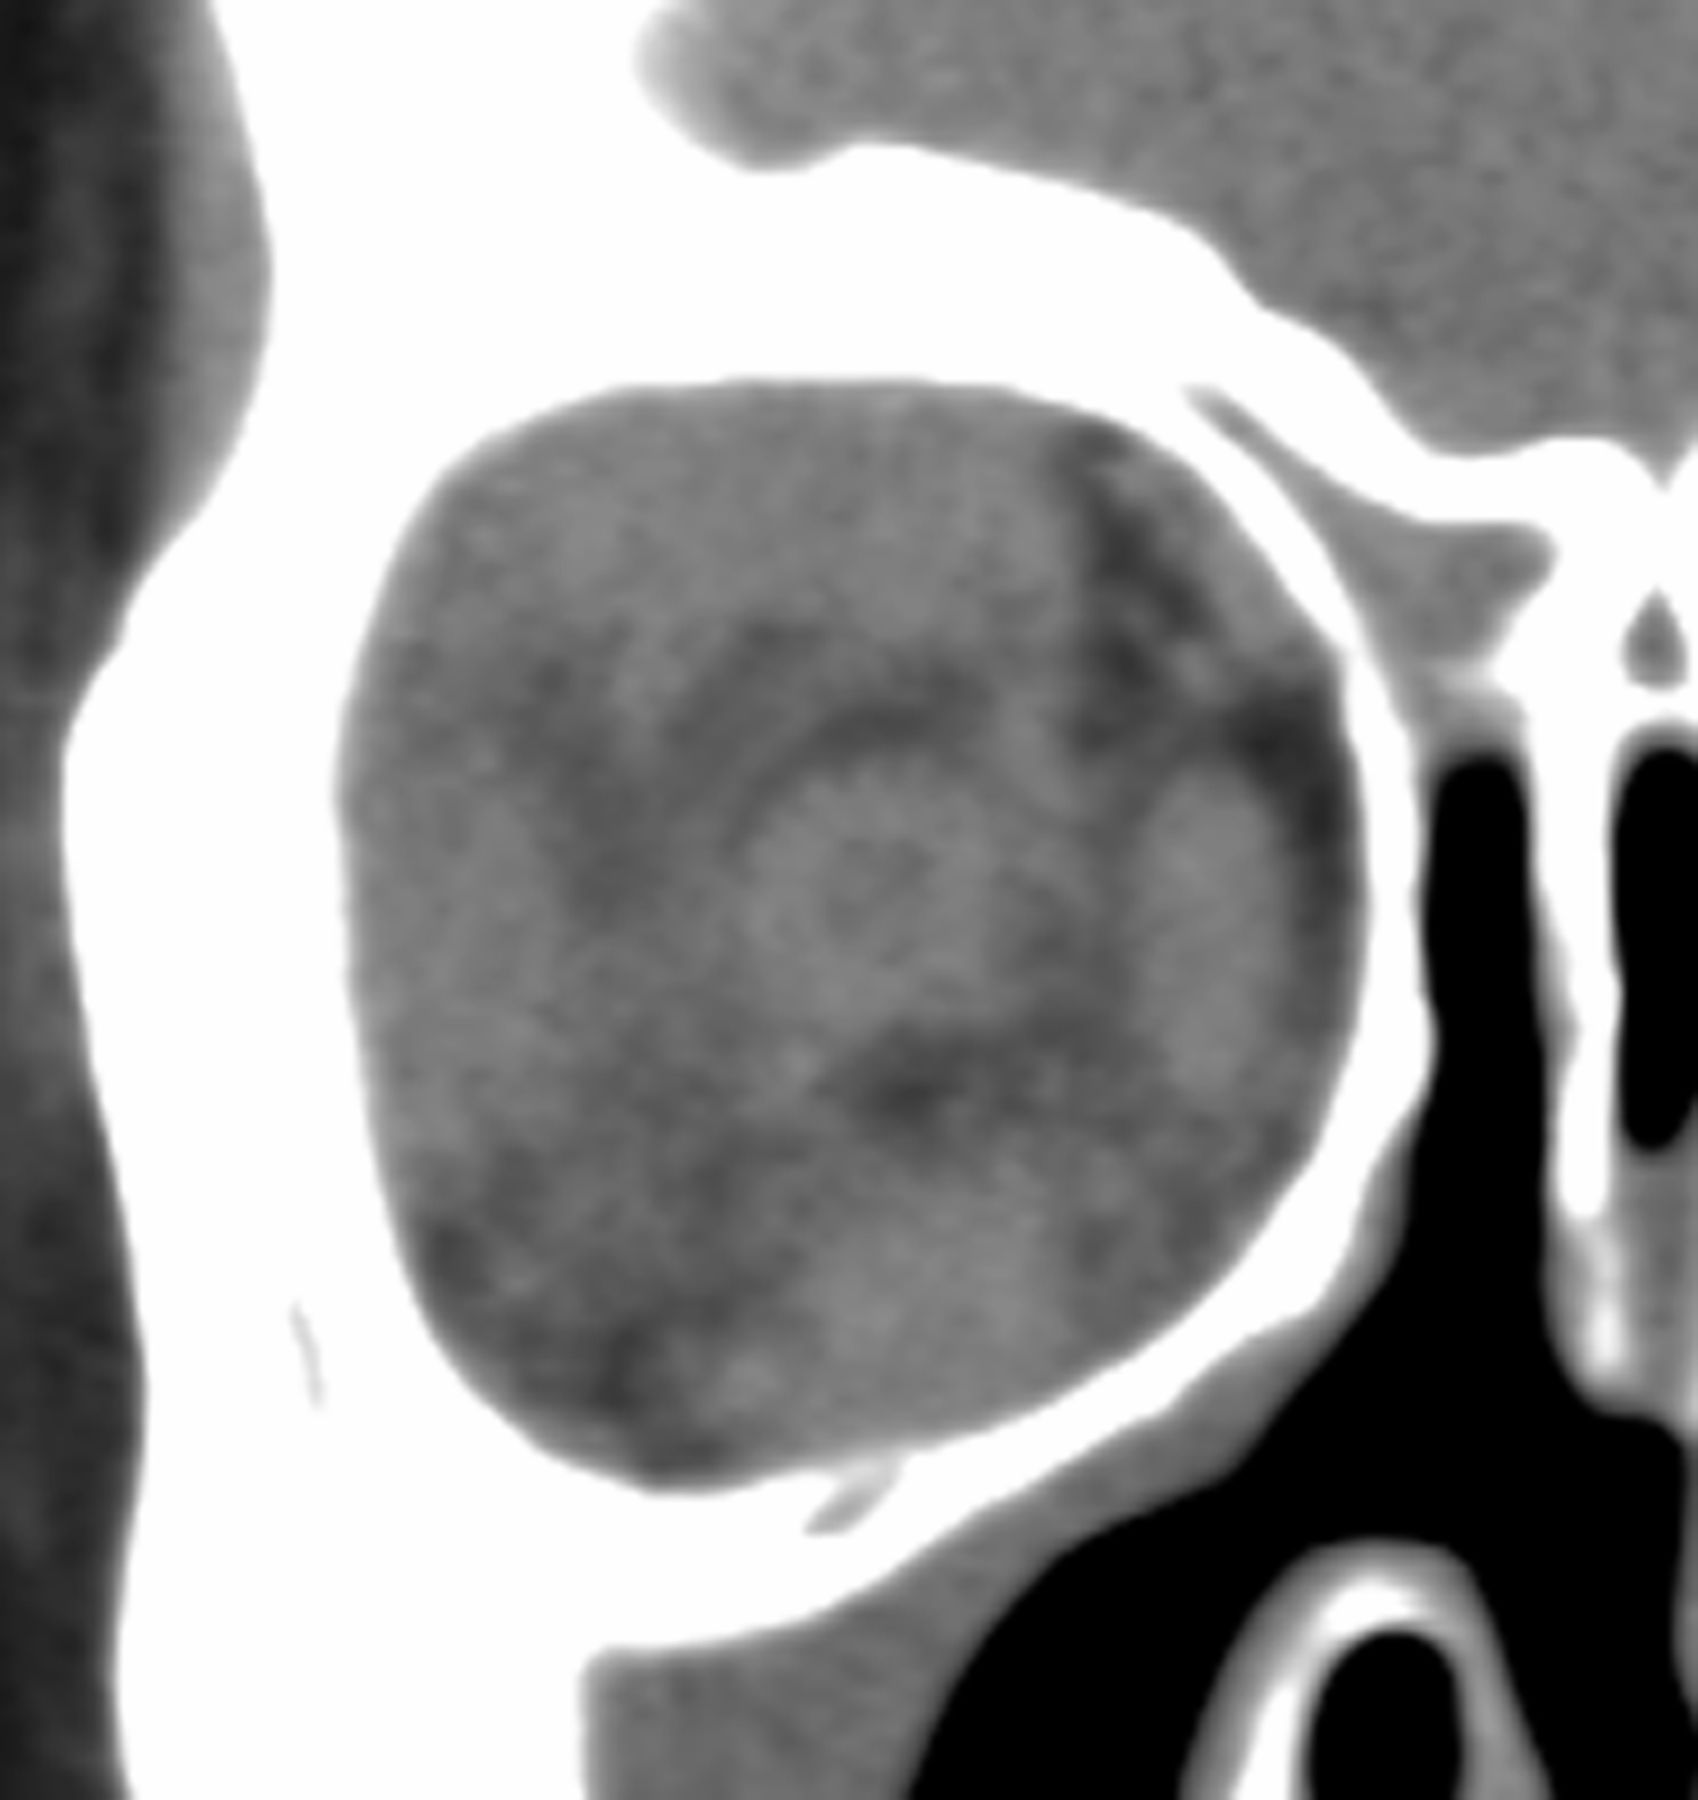

Twelve (44%) patients were characterized as having an infiltrative process within the orbital fat (Fig 3). Eight (30%) patients had infraorbital nerve enlargement (Figs 1B and 4), 5 (63%) of which were bilateral. Three (11%) patients had intracranial IgG4 involvement, 1 bilateral and 2 unilateral (Fig 5). Both patients with unilateral involvement had unilateral soft-tissue masses within the cavernous sinus. The patient with bilateral involvement had soft-tissue masses within the cavernous sinuses and anterior Meckel cave. Fifteen (63%) patients had documented IgG4-related lesions outside the orbit, 11 (73%) of which were outside the head and neck. Other areas of involvement documented in the electronic medical record included lymph nodes (cervical, thoracic, and abdominal), parotid glands, autoimmune pancreatitis, and hepatic pseudotumor. Paranasal sinus mucosal thickening was seen in 24 (89%) patients, as demonstrated in Fig 1.

Infiltrative orbital process in a 42-year-old woman with IgG4-related ophthalmic disease.